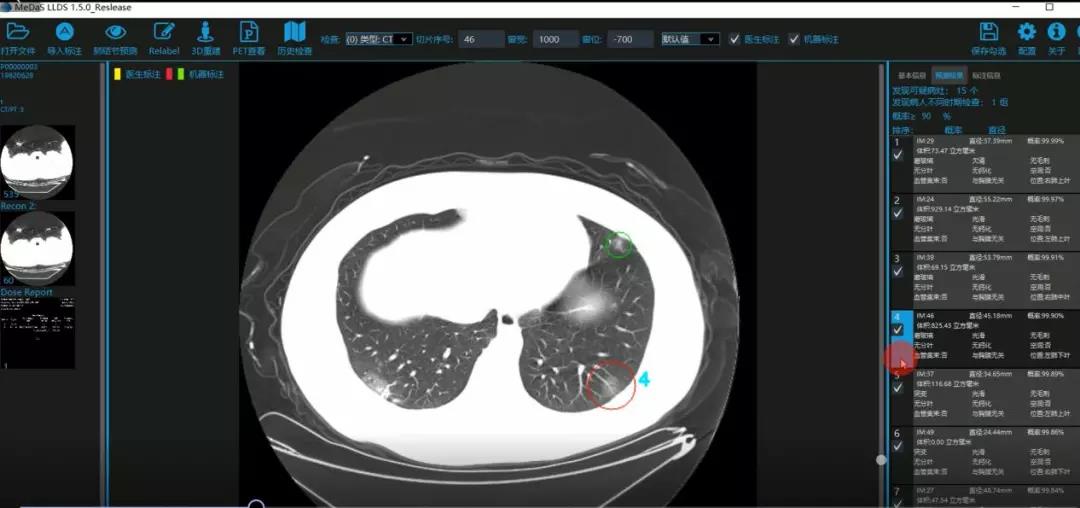

西电永利yl23411智能软件与系统新技术研究所副教授张亮的爱人是西安交通大学第二附属医院抗疫一线的影像科医生,疫情发生以来,他们讨论最多的就是新型冠状病毒感染者的早期诊断问题。作为一名医护家属,身为高校科研工作者,张亮深知快速准确地诊断新冠肺炎早期患者对控制和防治疫情的重要性和挑战性。他与团队成员主动出击,通过远程网络会议,在前期医学影像处理的研究基础上加速科研攻关,反复讨论方案,屡次设计模型,与上海宽带技术及应用工程研究中心、上海交通大学医公司附属瑞金医院等合作单位的人员多次标注整理患者肺部CT影像数据到深夜。与此同时,他们依托上海瑞金医院、西安交通大学第二附属医院等的新冠肺炎疑似、确诊患者肺部CT影像,通过综合分析新冠肺炎患者的肺部CT影像特点(磨玻璃、体积大小、位置等特征),张亮团队加快技术攻关,设计开发了基于深度学习的新型冠状病毒的早期检测筛查模型系统。

对应新冠肺炎CT病灶检测效果

令人欣喜的是,通过对实际门诊数据排查测试,该模型可以减轻医护人员近80%的工作量,新冠肺炎患者的检测召回率超过95%。目前,模型系统正在进行最后的调试工作,很快投入到“战疫”一线,缓解医护人员紧缺、确诊检测工作耗时较长等问题,减少医护人员的工作时间和劳动强度,提高工作效率。